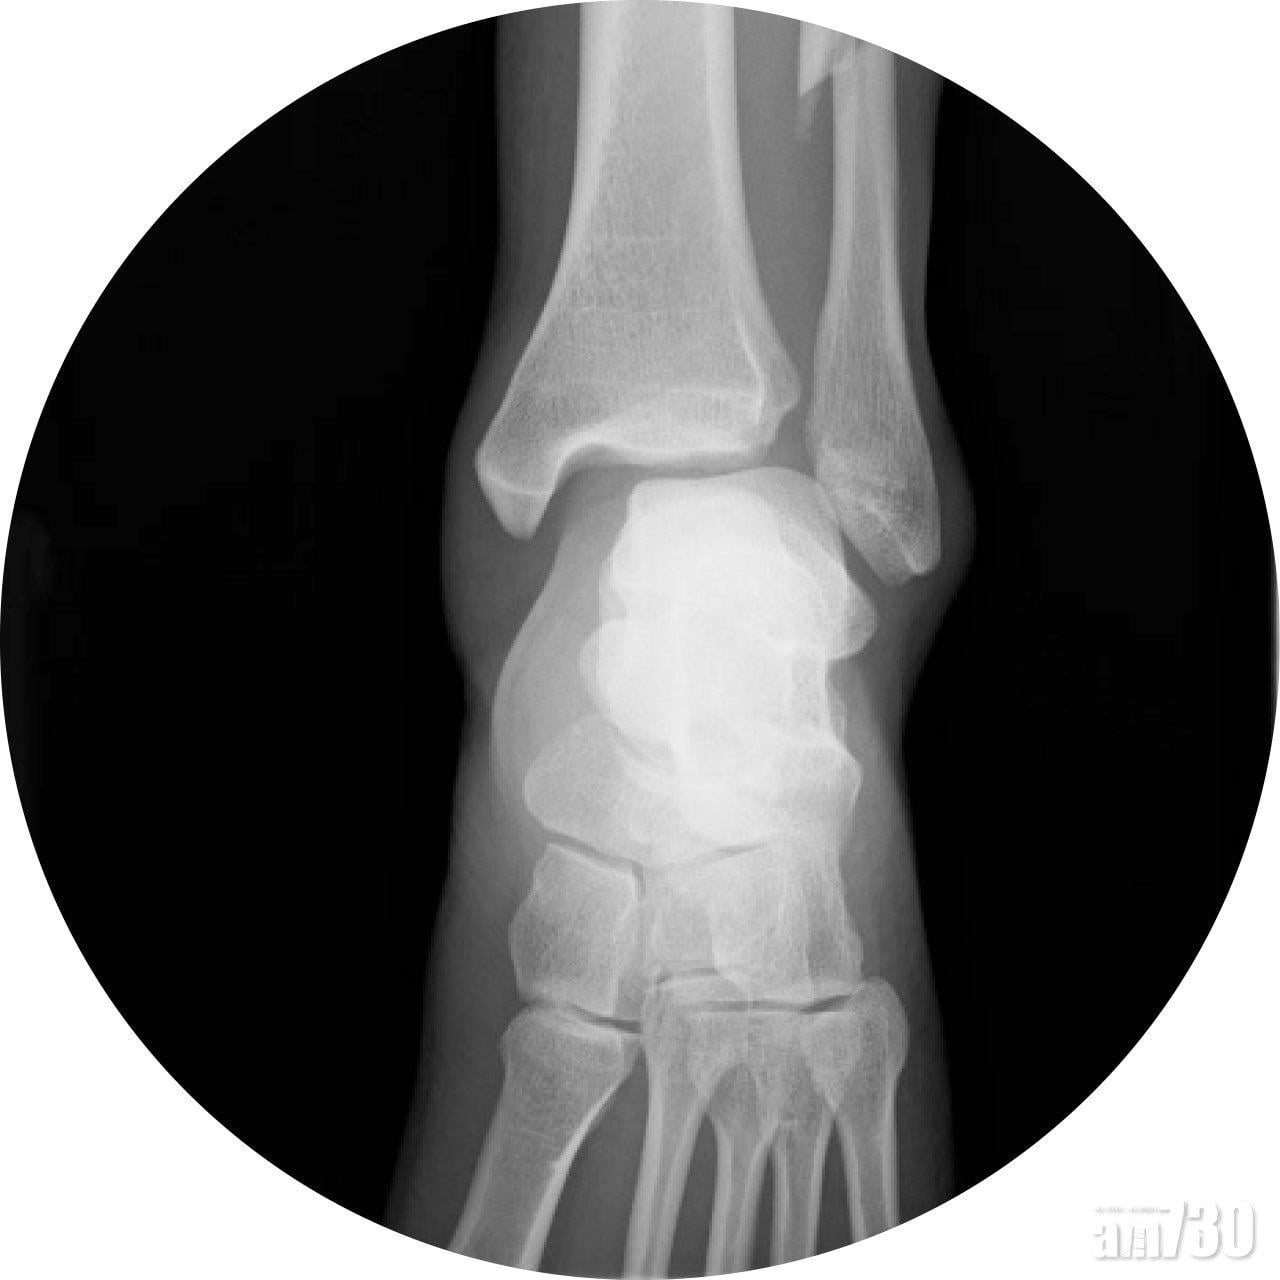

運動科學的範疇相當廣闊,包括了解剖學、生物力學、運動生理學、運動醫學、營養學、心理學等多方面的知識。當應用在運動訓練時,使用最有效的方法來提升運動表現。例如每個人不同的體型和身體結構,運動時各關節和肌肉之間的角度、協調等,皆可以影響到動作的有效性和身體所承受的壓力,這都是解剖學和生物力學所研究的課題。不同的訓練次數、強度、時間、以及訓練和休息之間的平衡等都對身體有不同的刺激,從而影響到訓練的效果,這就是運動生理學。運動醫學方面,主要是監察運動者的健康狀況、治療運動所引致的創傷和勞損、防治措施和傷後的康復訓練等。適當的營養補充,可有效地控制運動者的體重達致最佳水平,同時亦可確保攝取的營養足以應付訓練、比賽與恢復的需要。運動心理學能協助運動者有關心理控制的技巧,以最佳心理狀態下應付訓練或比賽時的壓力。所以,絕對不是有兩條腿就懂跑步,運動除了須要體力,還須要腦力。